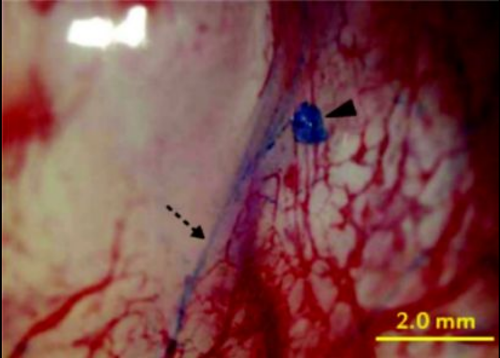

2008년에는 국내 연구진이 나노형광입자로 프리모관을 염색하는 데 성공하면서 연구가 가속화됐다. 2008년 소광섭 서울대 물리천문학부 교수 연구팀이 '트라이판 블루'로 프리모관을 염색, 가늘고 투명한 프리모관을 찾아낸 것이다.

이 때문에 서양의학의 원리로 경락의 존재를 입증하고자 하는 시도가 뒤따랐다. 김봉한 교수는 인간의 몸 속에 혈관계와 림프계에 이어 제3의 순환계가 존재하고, 세포보다 더 작은 '산알'이 조직의 재생에 관여한다고 주장, 이와 관련해 1963년 '경락계통에 관하여', 1965년 '경락체계'등의 논문을 발표했다. 경락과 경혈이 피부뿐만 아니라 몸 속에도 존재하고 있다는 주장을 편 것이다. 또한 그는 경락경혈의 실체를 찾던 중 일종의 푸른색 염색약으로 경혈점이 염색된다는 사실을 발견한 것으로 알려졌다.